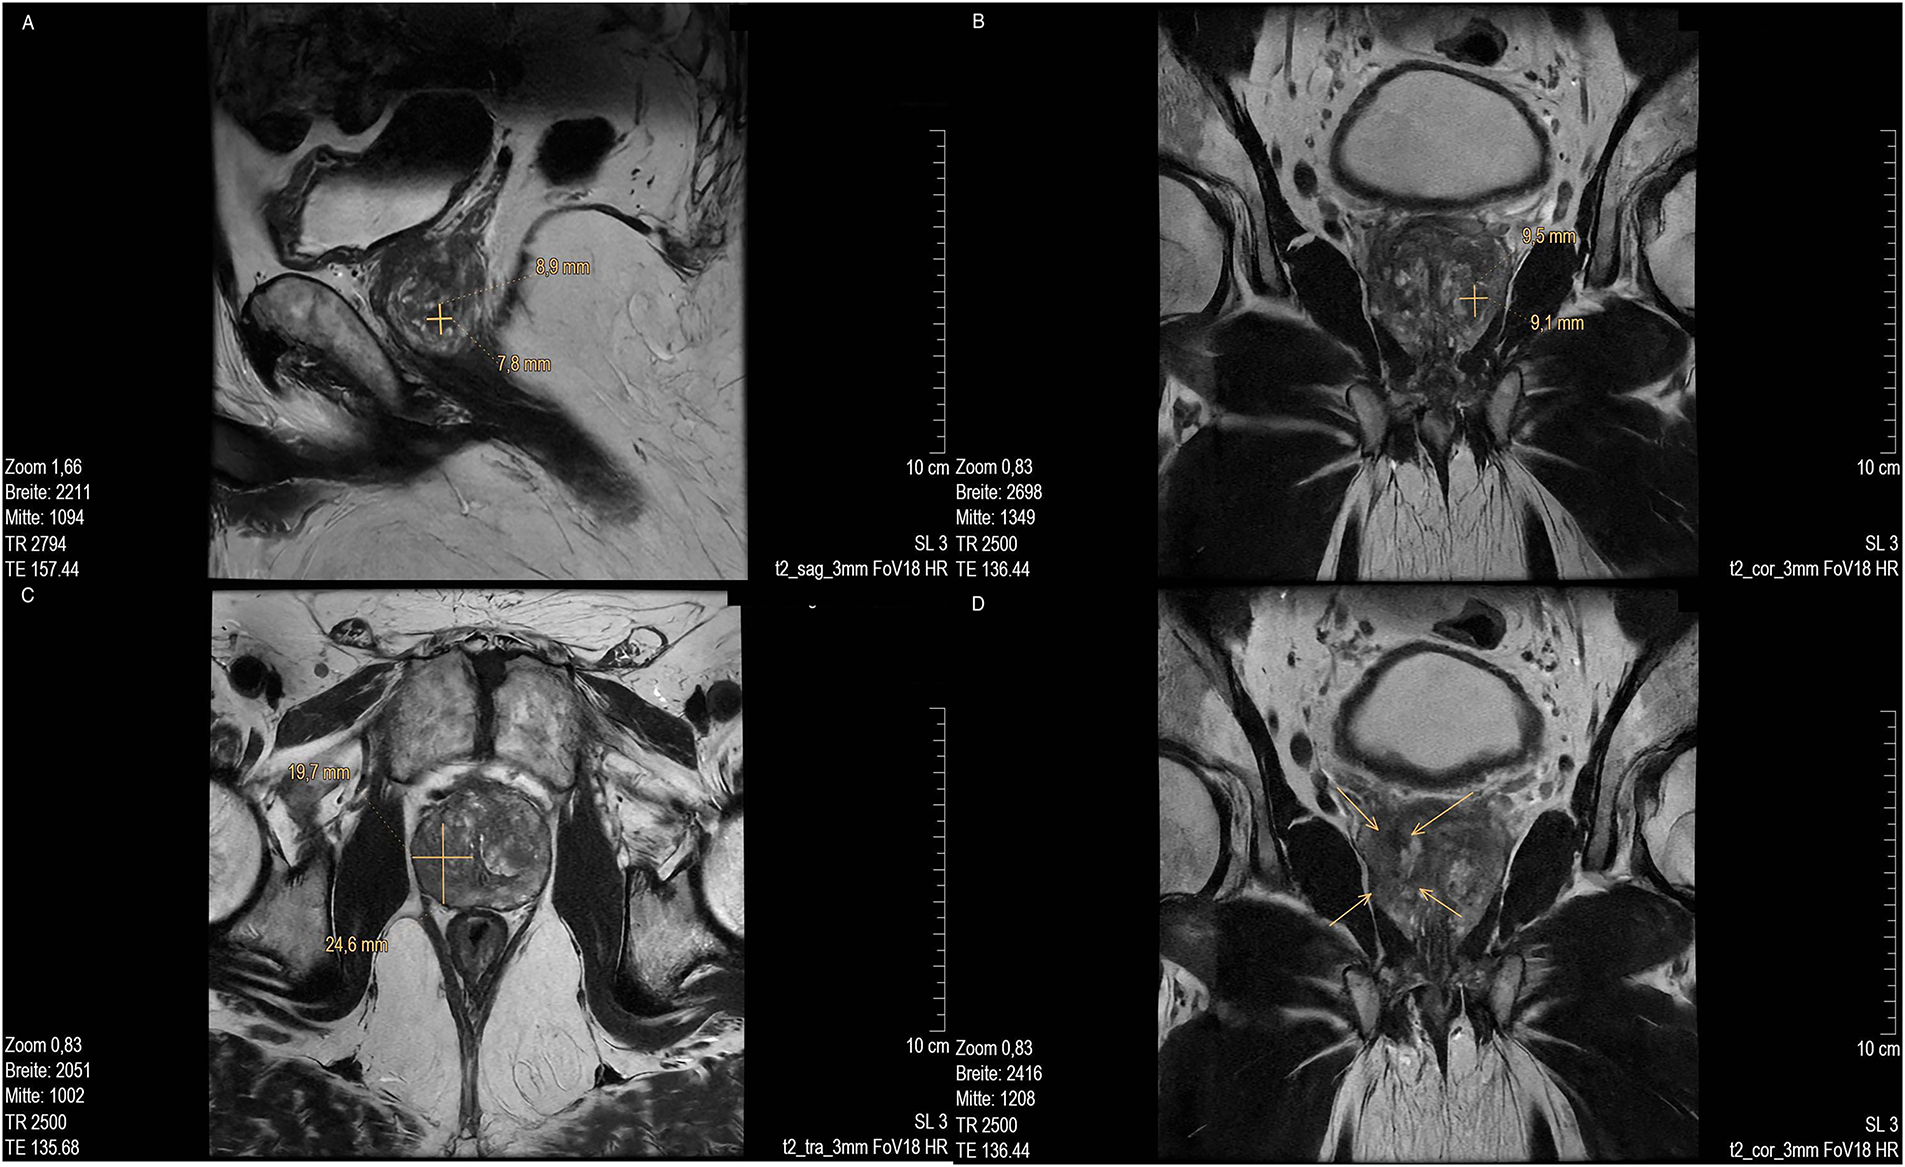

MR imaging revealed several suspicious lesions (Figs. 2 and 3) in the prostate gland and a wall thickening of the urinary bladder.

Figure 3: MRI scan of prostate of lesion 3. (A) Low in signal in T2 sag 3 mm FOV 18 and (marked with cross); (B) T2 cor 3 mm FOV 18. MRI of lesion 4 (marked with cross); (C) T2 tra 3 mm FOV18 (marked with cross) and (D) Low signal in T2 cor 3 mm FOV18 (marked with arrow). MR images courtesy of Dr. med. Stefan Oehm from die Radiologen, Weiterstadt, Germany. MRI, Magnetic Resonance Imaging; sag, sagittal; FOV, field of view; cor, coronal; tra, transverse

MRI showed an enlarged prostate gland (53 mm× 52 mm× 37 mm) depicted in Fig. 2A. A stromatous as well as adenomatous benign prostatic hypertrophy was visible. Lesion 1 is at a 9- to 10-o’clock position (marked with an arrow), located in the transitional/central zone, approximately 10 mm in size, without sharply defined edges and with a low signal in T2 sagittal (sag) 3 mm field of view (FOV) 18. The diffusion weighted imaging (DWI) displayed signal rich increasing b-values. The apparent diffusion coefficient (ADC) showed a low signal. In the perfusion study, increased perfusion with post initial contrast increase and wash-out was observed. Lesion 2 was located at approximately. 5- to 6-o’clock position (Fig. 2B, marked with an arrow) in the peripheral zone, close to the capsule, and about 11 mm in length (marked with a bar). Low signals were detected in T2 transverse (tra) 3 mm FOV 18. The lesion presented as planar, smoothly limited with a broad capsule contact. As for Lesion 1, Lesion 2 also displayed a rich signal in the DWI with increasing b-values, and a low signal in the ADC. No pathological accumulation of contrast agent was detectable. At approximately the 4 o’clock position, lesion 3 (marked with an arrow) was discernible in the transition zone with a length of ~10 mm. Low signal in T2 (Fig. 3A,B). Again, a rich signal was detectable in the DWI with increasing b-values, as well as a low signal in the ADC. In the perfusion study, post initial rapid enhancement with washout was observed. Lesion 4 is likely to correspond to the index lesion (area in Fig. 3C about 620 mm2, marked by arrows). A two-dimensional signal lowering from the transitional/peripheral zone to the central zone on the right side at 6- to 11-o’clock (Fig. 3C) was observed. This area also included large portions of the contralateral left peripheral zone, which was low in signal. The diagnostic finding showed a blurred border and a wide capsular contact, especially in the right circumference. In T2 (Fig. 3C,D) and the DWI, a low signal could be seen. The ADC also showed a flat low signal. No increased perfusion was detected. Based on the MRI data, lesions 2 and 3 were classified as PI-RADS 4, whereas lesions 1 and 4 were classified as PI-RADS 5 due to their morphology.